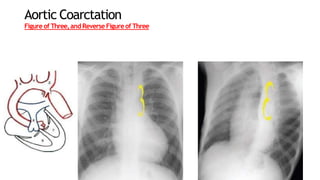

AorticCoarctation

• Classic radiologic signs

• Figure-of-three sign

• Reverse figure-of-three sign

Aortic Coarctation

Figureof Three,and Reverse Figureof Three

AorticCoarctation • 5%–10% ofcongenital cardiac lesions • Produced by a deformity of the aortic media and intima, which causes a prominent posterior infolding of the aortic lumen • Occurs at or near the junction of the aortic arch and the descending thoracic aorta • Infolding cause eccentric narrowing of the lumen at the level where the ductus or ligamentum arteriosus inserts anteromedially • Resultant luminal narrowing in turn obstructs the flow of blood from the left ventricle • Classic radiologic signs • Figure-of-three sign • Reverse figure-of-three sign